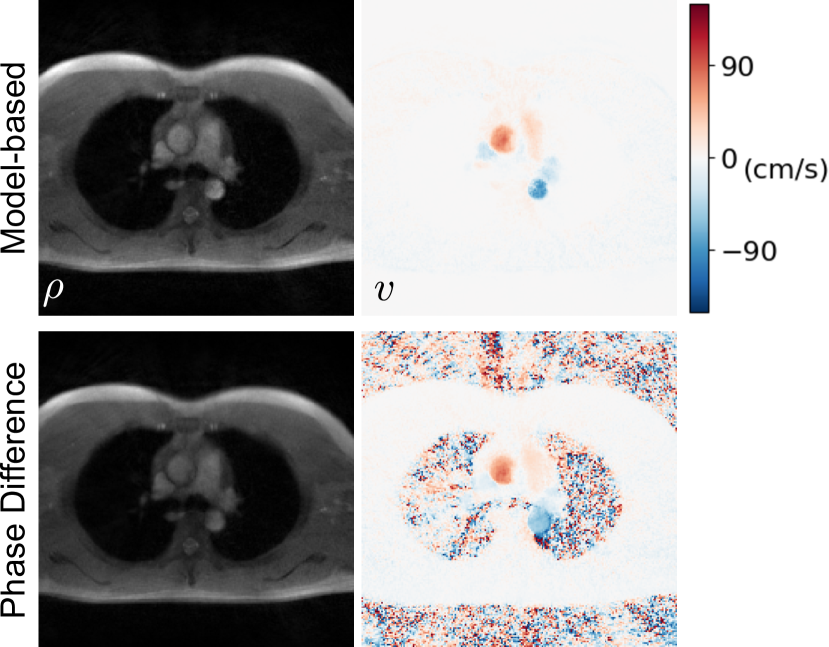

As an example, flow MRI sequence with radial sampling and through-plane velocity-encoding gradient was used to measure aortic blood flow velocities. As shown in Fig. 4, with direct regularization on the phase-difference map, the proposed model-based reconstruction [11, 30] is able to largely remove background random phase noise. Supplementary Video 4 displays the dynamic velocity maps of the whole 15-second scan.

Refer to caption

Figure 4: Comparison between (top) the model-based reconstruction and (bottom) the conventional phase-difference reconstruction. A section crossing the ascending and descending aorta was selected as the imaging slice. Displayed images are (left) anatomical magnitude image and (right) phase-contrast velocity map at systole. With direct phase-difference regularization, the model-based reconstruction largely reduces random background phase noise in the velocity map.